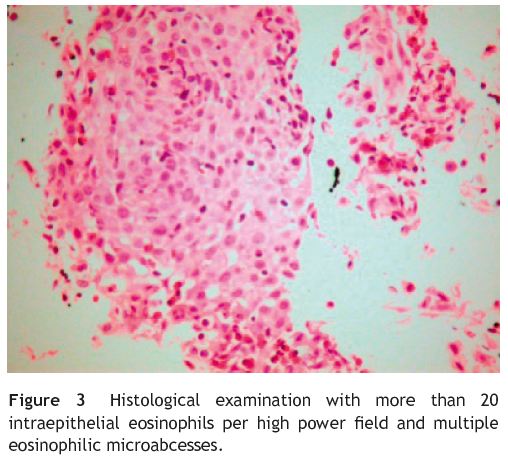

Eosinophilic esophagitis is defined as a clinicopathologic entity, combining clinical data on (1) relevant symptoms (distinct in the pediatric or adult populations, with mostly food impaction and dysphagia in adults and feeding intolerance, failure to thrive and gastroesophageal reflux disease (GERD) symptoms in children and adolescent); (2) esophageal biopsies with adequate histologic findings (≥20 eosinophils/ high-power field); and (3) exclusion of other diseases with overlapping features, especially GERD.1

Because of persistent heartburn that did not improve with appropriate medical treatment and taking in to account her past asthmatic history, eosinophilic esophagitis was suspected. Upper gastrointestinal endoscopy was then repeated and again revealed normal-appearing mucosa of esophagus, stomach and duodenum. Notwithstanding, biopsies were obtained from the proximal and distal esophagus. Histological examination revealed more than 20 intraepithelial eosinophils per high power field and multiple eosinophilic microabcesses (Fig. 3), both diagnostic of eosinophilic esophagitis. Biopsies from stomach and duodenum were also obtained and histological findings were normal.

Marked eosinophil infiltration in the esophageal epithelia (>20 eosinophils per high-power field) is the diagnostic Hallmark and samples should be obtained from proximal and distal esophagus,1-4 even in normal appearing mucosa in endoscopy.5 In our case report, we found normal appearing mucosa at endoscopy, but esophageal biopsies revealed marked eosinophilic infiltration. Recently, a prospective study conducted by Prasad G. et al. concluded that midesophageal biopsies taken from normal-appearing mucosa in patients with unexplained solid food dysphagia may diagnose eosinophilic esophagitis in about one in 10 cases.6

Clinical and pathologic features of gastroesophageal reflux disease (GERD) and eosinophilic esophagitis may overlap.5 Both diseases share varying degrees of esophageal eosinophilia and some authors suggest that mucosal injury caused by acid reflux may allow swallowed allergens to penetrate esophageal mucosa causing mild eosinophilia.5,7 Gastroesophageal reflux disease is actually the most common cause of eosinophilic infiltration of the esophagus. However, GERD-related infiltrates tend to be less dense and the greatest number is in the distal esophagus, whereas the dense infiltrates of eosinophilic esophagitis are seen throughout the esophagus.5,7 Because of this possible overlap, the diagnosis of eosinophilic esophagitis should be made after acid reflux has been treated or excluded.1,5 Before we considered eosinophilic esophagitis diagnosis and performed esophageal biopsies, our patient tried a trial with pump proton inhibitor at maximum doses and a pH monitoring excluded pathologic gastroesophageal reflux. Therefore, our patient met all criteria for definitive diagnosis of eosinophilic esophagitis: clinical symptoms, compatible histology and lack of responsiveness to high-dose pump protón inhibitor with normal pH monitoring of the distal esophagus.